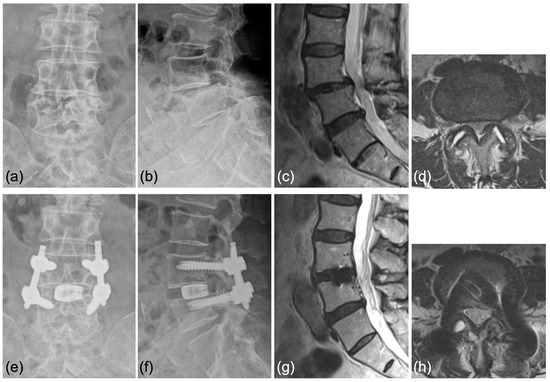

Case 1: A 70-year-old woman was diagnosed with degenerative spondylolisthesis of the L4 vertebra with instability by X-ray, CT, and MRI. VAS for back and leg pain were 100 and 60 mm, and the JOA score was 18/29. The spinal canal area was 95 mm2 at L4/5 disc level, and the % slip was 21% (Figure 7a–d). After the failure of conservative treatment, PETLIF was performed. One month after surgery, VAS back and leg pain improved significantly to 0 and 10 mm. Postoperative X-ray and MRI showed that the % slip was 0%, and the spinal canal area was expanded to 153 mm2 (Figure 7e–h). Bone fusion of L4/5 was confirmed by X-ray and CT scan one year after the surgery (Figure 8a–d).

Figure 7.

(a,b) Preoperative X-ray showing 2° L4 spondylolisthesis. (c,d) Preoperative MRI showed lumbar spinal stenosis at the L4/5 level. (e,f) Postoperative X-ray showed L4 spondylolisthesis was reduced to 0%. (g,h) Postoperative MRI showed the spinal canal area was expanded.